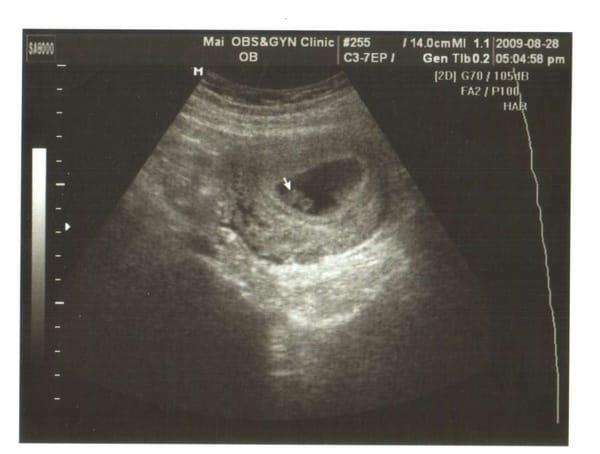

第二次產檢,驗尿ok,血壓ok,體重56.4。 護士衛教講解,上次驗血都ok,下次要做唐氏症檢驗,這次分兩種,一個是傳統的1000、另一種是四指標2200,兩個價格差1200。自己選要傳統的還是四指標。 另外還有脊髓性肌肉萎縮症看是否要一起驗血檢驗,自費2000。 這次真多了一些自費檢驗的項目啊! 下午四點多,候診室裡人很少,很快就輪到我看診。 躺上檯子,超音波裡我看 […]…